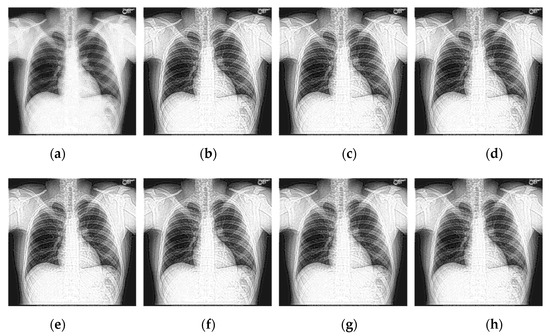

Select two representative medical images for analysis: Image 1 with the size of 440 × 440 and image 2 with the size of 1024 × 1024 . The enhanced X-ray images obtained under different decomposition levels are shown in Figure 3 and Figure 4 where (a) is the original image, and (b–f) corresponds to the decomposition levels j equal to 1–5. When the number of scale decomposition levels is j , NSST decomposition requires 2 j times of image and filter convolution; the running time of the algorithm gradually increases. Observing the image, the image contrast has been significantly improved after histogram equalization. When the decomposition scale j 3 , with the increase of the NSST decomposition scale, the boundary and texture features of the image are gradually obvious, and the detailed information is enhanced. When 5 j > 3 , the enhancement effect is further improved; the change is not significant.

Figure 4. The enhanced effects of different decomposition levels on the X-ray image 2. (a) is the original image, and (bf) corresponds to the decomposition levels j equal to 1–5.